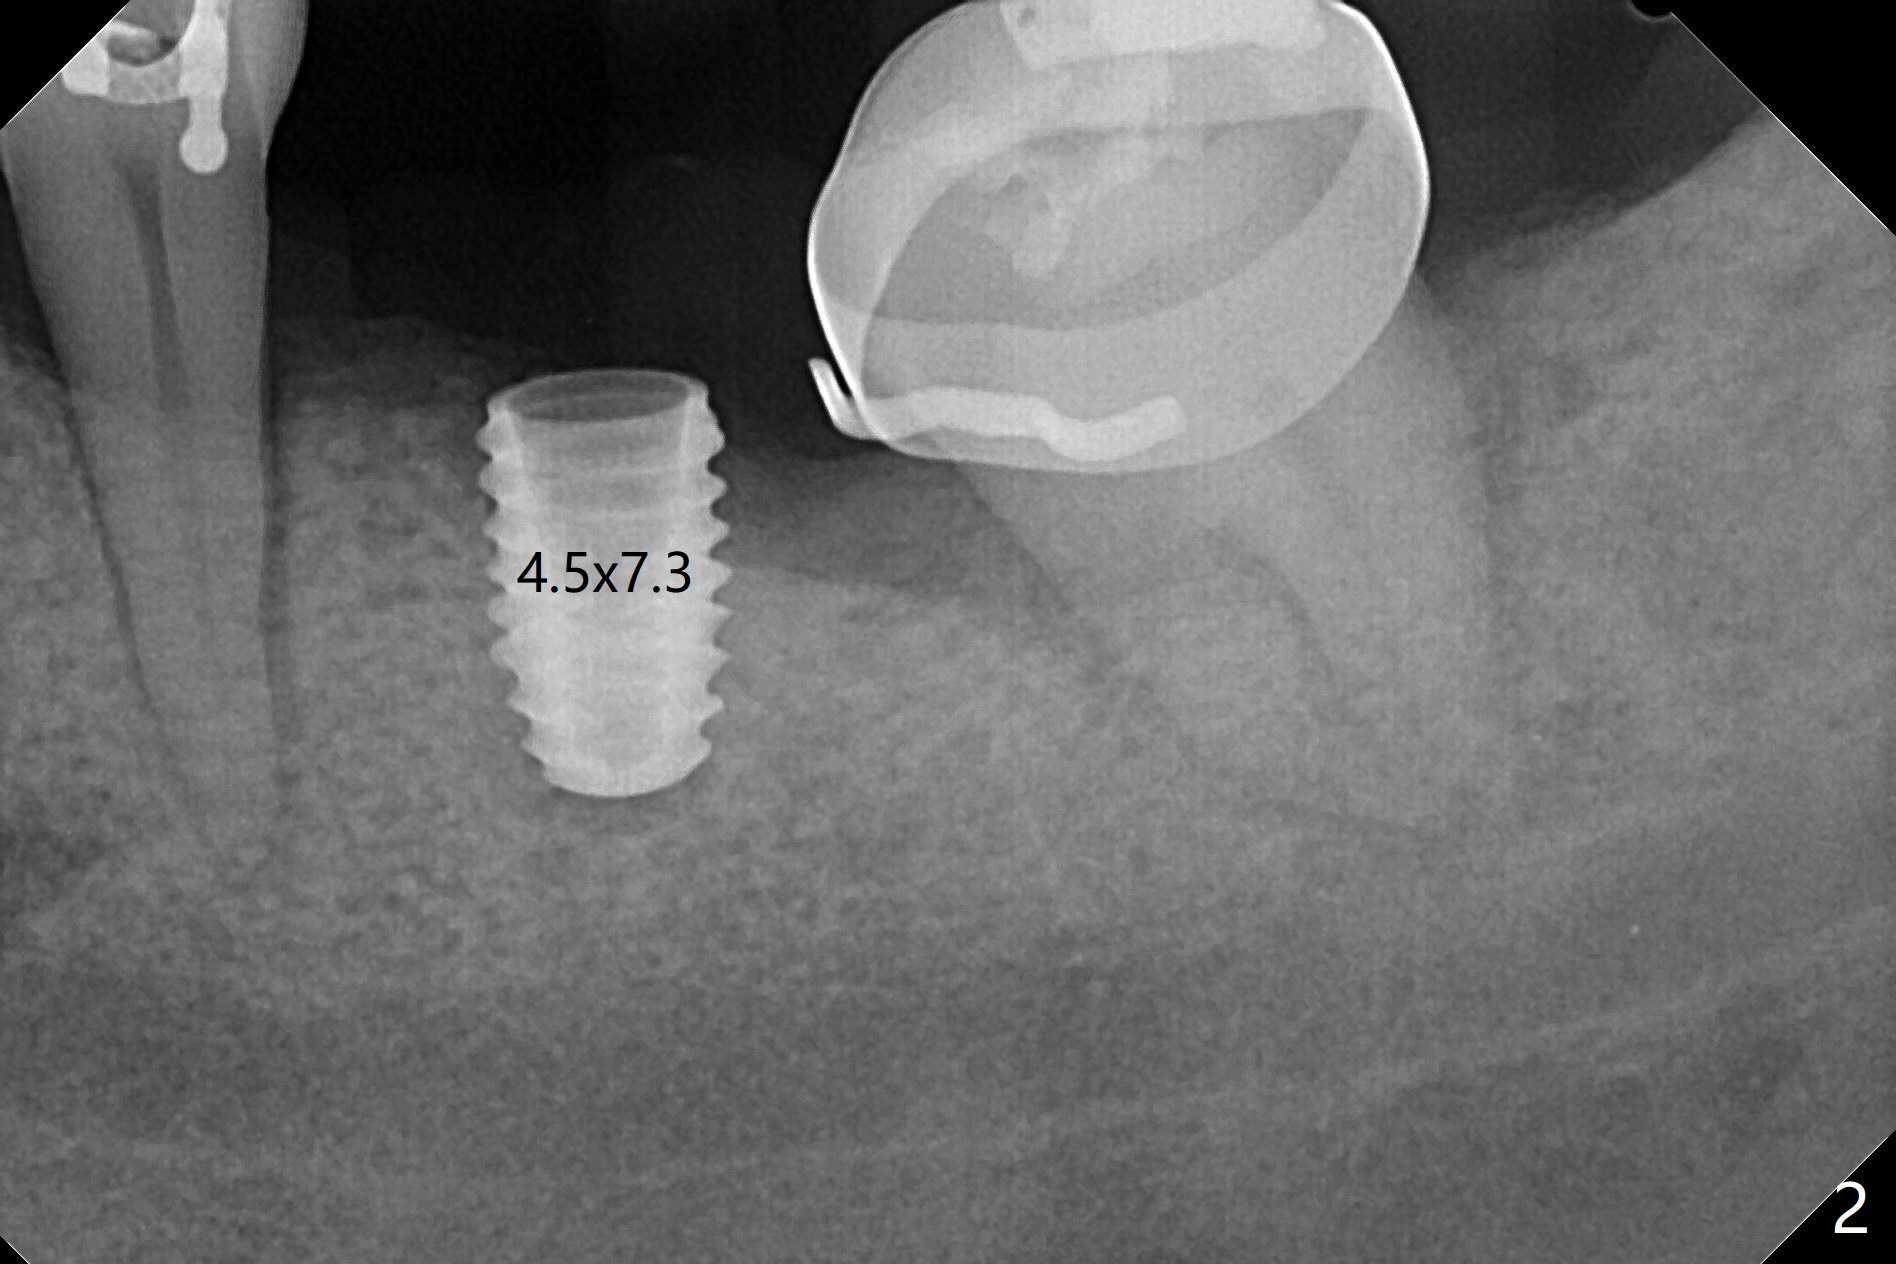

31岁女19号牙残根拔除,没有植骨,牙齿矫正创造了大约近远中10.5毫米空间,先锋钻深度8毫米(图一),远中舌侧骨质缺损(*)。使用4x7.3毫米钻头(实际长度8.5毫米)后,植入4.5x7.3毫米植体,远中大约3个螺纹暴露(图二)。使用4x8.5毫米钻头后,植体种深些(图三),但是根尖仍有空间(*)。再种深后(只有一个螺纹暴露),放置基台和粘性骨粉(图四:*),覆盖PRF,缝合,放置矫正钢丝和牙周敷料。